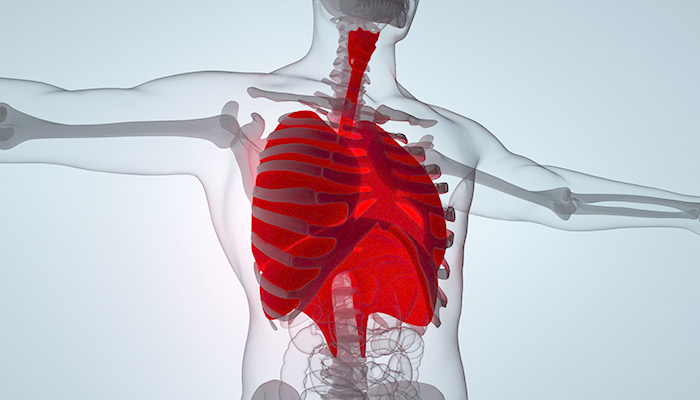

二氧化氯对健康危害极大,在气态或者高浓度液态时,具有很强的刺激性,接触后会引起眼和呼吸道刺激,引起一系列的呼吸系统疾病,严重可导致肺水肿和呼吸衰竭,有致死的危险。皮肤接触或摄入高浓度溶液,可能会引起刺激和腐蚀,长期接触可导致慢性支气管炎。

二氧化氯对健康危害极大,在气态或者高浓度液态时,具有很强的刺激性,接触后会引起眼和呼吸道刺激,引起一系列的呼吸系统疾病,严重可导致肺水肿和呼吸衰竭,有致死的危险。皮肤接触或摄入高浓度溶液,可能会引起刺激和腐蚀,长期接触可导致慢性支气管炎。